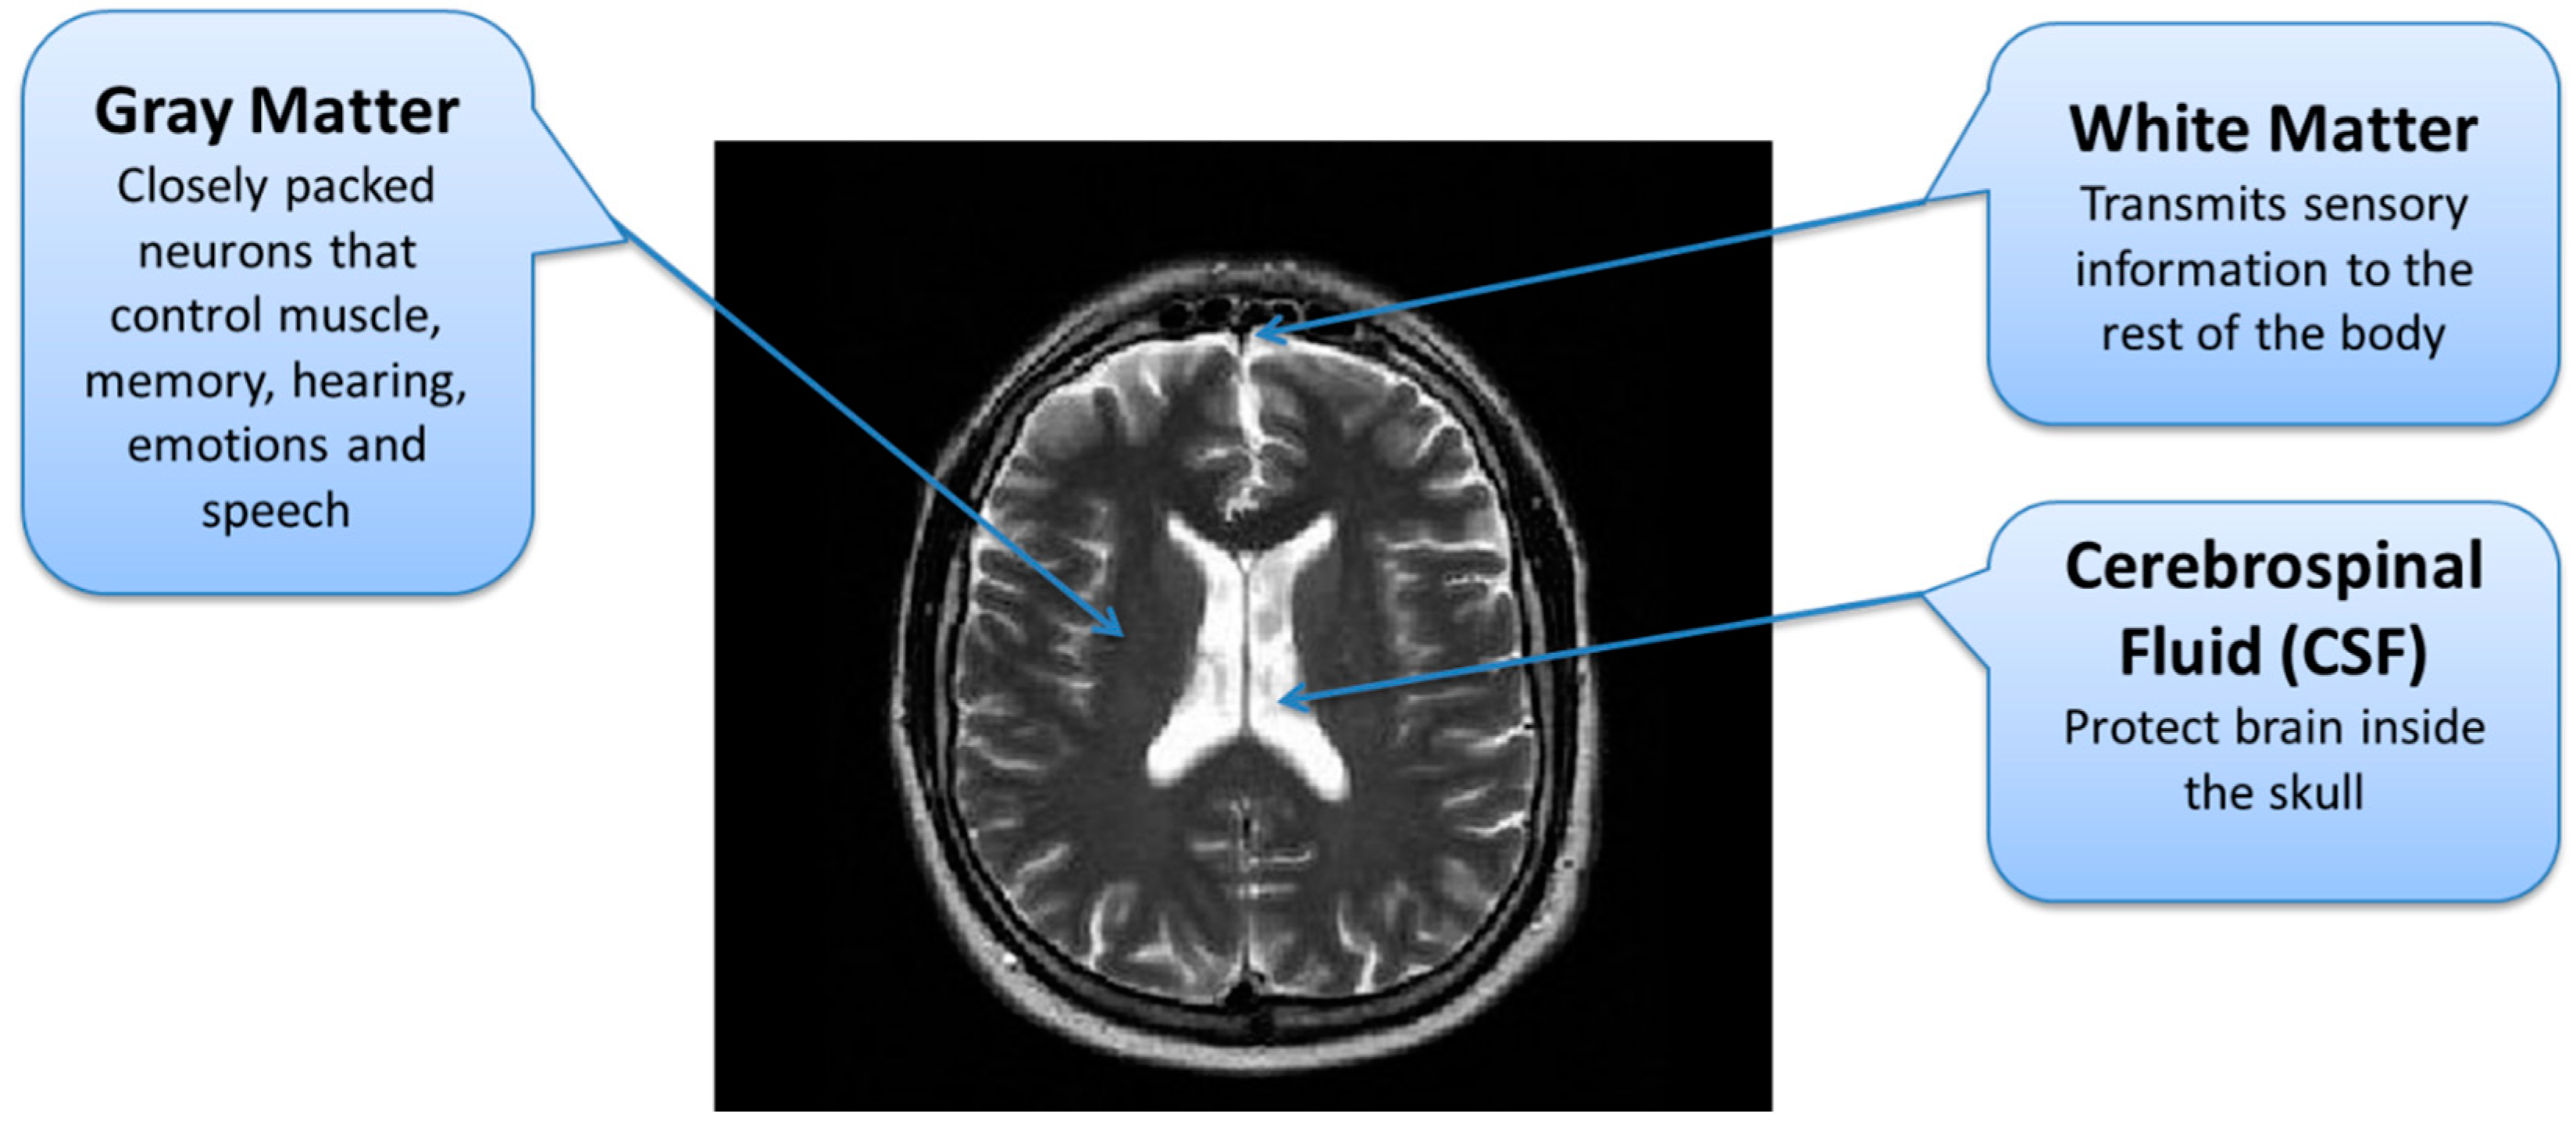

In the second stage, tumor regions were extracted from the tumorous images. Segmentation of brain tumor is a very complex task because of the complex anatomy of the brain structure [24]. Due to the low contrast and correlated MR scans, the segmentation task becomes highly complicated. For a comprehensive analysis of brain tumors from MR images, different patterns of effective parts of the brain are required through which the tumorous part can be differentiated from the rest of the brain. A brain can be divided into three main parts; Cerebrospinal Fluid (CSF), Gray Matter (GM), and White Matter (WM) [25]. The important task during the segmentation of brain MR images is to partition these tissues correctly. Hence, voxels’ labeling for specific tissue types carries immense importance in MR image segmentation [26]. As described earlier, the low contrast of brain MR images is another issue due to which it is difficult to differentiate among these three tissue types. The brain tissue overlapping issue is mainly addressed using FCM-based brain tumor segmentation technique.

Figure 4. Brain MRI Tissues Types.